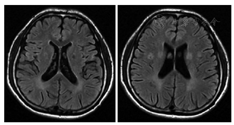

辅助检查:血、尿、粪常规,凝血功能、铜蓝蛋白和结缔组织未见异常;生化:甘油三酯1.07 mmol/L(正常值0.56~1.70 mmol/L),低密度脂蛋白1.56 mmol/L(正常值2.7~3.1 mmol/L),高密度脂蛋白1.21 mmol/L(1.16~1.55 mmol/L),总胆红素4.7 μmol/L(正常值5.5~27.5 μmol/L),直接胆红素1.92 μmol/L(正常值0~8.60 μmol/L),非结合胆红素2.78 μmol/L(正常值5.50~18.90 μmol/L),天冬氨酸氨基转移酶26.6 U/L(正常值15.0~40.0 U/L),丙氨酸氨基转移酶22.7 U/L(正常值9.0~50.0 U/L),碱性磷酸酶91 U/L(正常值45~125 U/L),肾功能、电解质均正常。头颅MRI提示双侧侧脑室后角旁异常信号,考虑脑白质变性疾病可能性大(图2)。腹部超声:脾大(长径约14.6 cm,厚径约4.5 cm)。骨髓涂片结果:粒系增生明显涂片中可见尼曼-匹克细胞及海蓝组织细胞(图3)。因患者不能配合,未完成MMSE、蒙特利尔认知评估量表(MoCA)等相关量表评估认知功能。结合患者临床表现、辅助检查提示多系统病变以及知情同意下的骨髓穿刺结果,临床疑诊"尼曼-匹克病",经患者家属同意后将该家系行基因检测(图4):患者基因测序结果为NPC1基因外显子23有1个纯合突变c.3493G>A(p.V1165M),为错义突变;患者父亲及母亲进行Sanger一代测序验证,发现其父亲及母亲均携带该致病突变;对患者哥哥及姐姐进行验证,均未携带该致病突变。治疗上给予美多巴、盐酸苯海索、营养神经等对症治疗。患者依从性差,服药1周后再次自行停药。于2017年7月因进行性睡眠障碍,左前胫骨疼痛,严重影响患者生活第3次就诊我科。专科体检:双侧眼球垂直及水平活动受限,余体检结果同2017年4月。辅助检查:血常规未见明显异常;生化:甘油三酯0.72 mmol/L(0.56~1.70 mmol/L),低密度脂蛋白1.44 mmol/L(正常值2.70~3.10 mmol/L),高密度脂蛋白1.56 mmol/L(正常值1.16~1.55 mmol/L),总胆红素3.9 μmol/L(正常值5.5~27.5 μmol/L),直接胆红素2.9 μmol/L(正常值0~8.6 μmol/L),非结合胆红素1.0 μmol/L(5.5~18.9 μmol/L),天冬氨酸氨基转移酶49.4(U/L正常值15.0~40.0 U/L),丙氨酸氨基转移酶55.3 U/L(正常值9.0~50.0 U/L),碱性磷酸酶106.0 U/L(正常值45.0~125 U/L),肌酸激酶459 IU/L(正常值50~310 IU/L),肌酸激酶同工酶30.9 IU/L(正常值0~250.0 IU/L)。左侧胫腓骨正侧位片:左侧胫腓骨骨质结构未见明确异常。继续给予药物对症治疗。电话随访发现患者在出院1周后死亡。